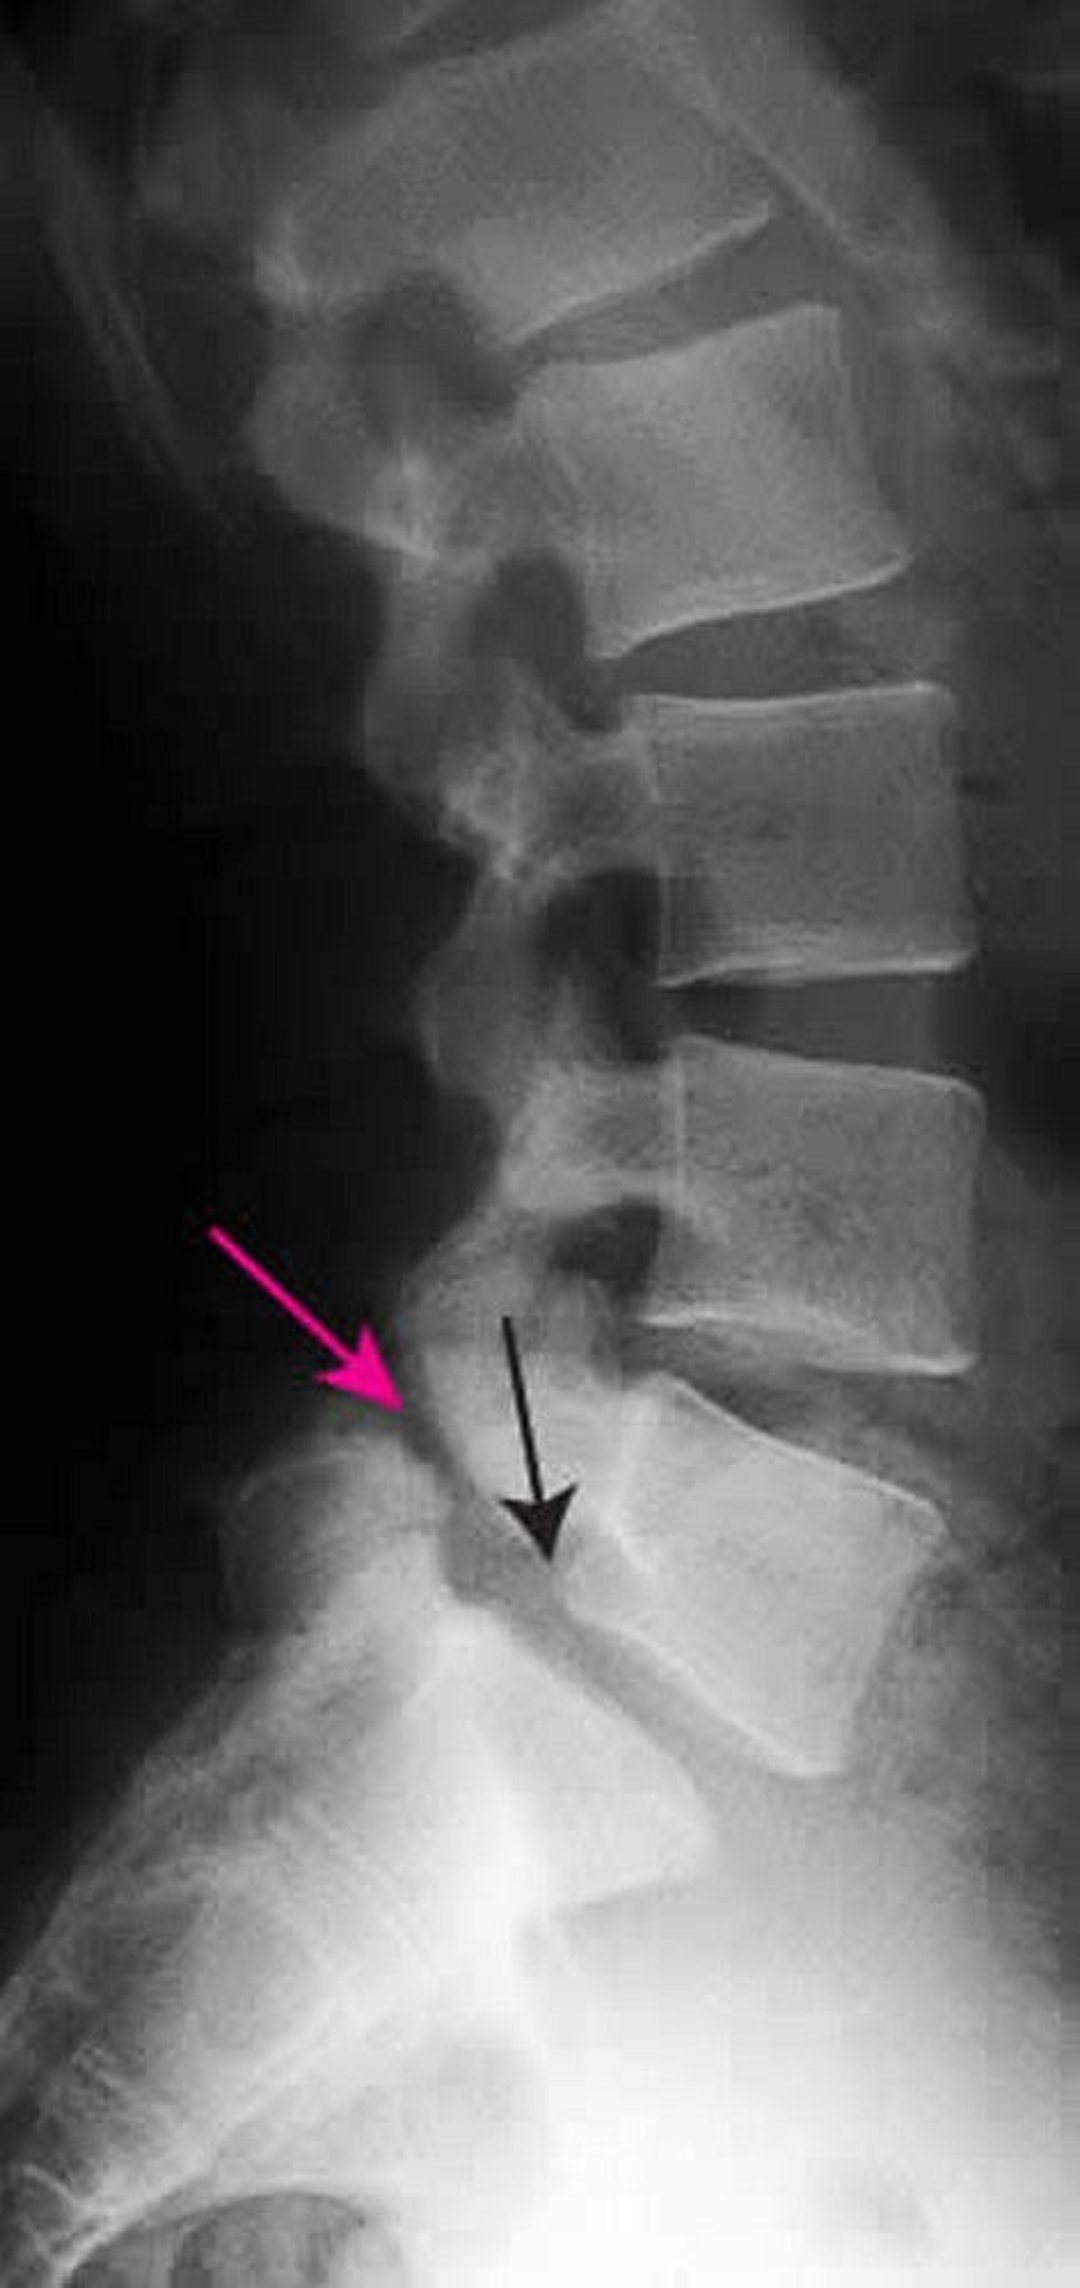

Spondylolisthesis

This radiograph shows grade 1 spondylolisthesis of L5 on S1. The black arrow shows the posterior border of L5, which subluxes anterior to S1. The red arrow points to the spondylolysis (defect in the pars interarticularis).

ZEPHYR/SCIENCE PHOTO LIBRARY